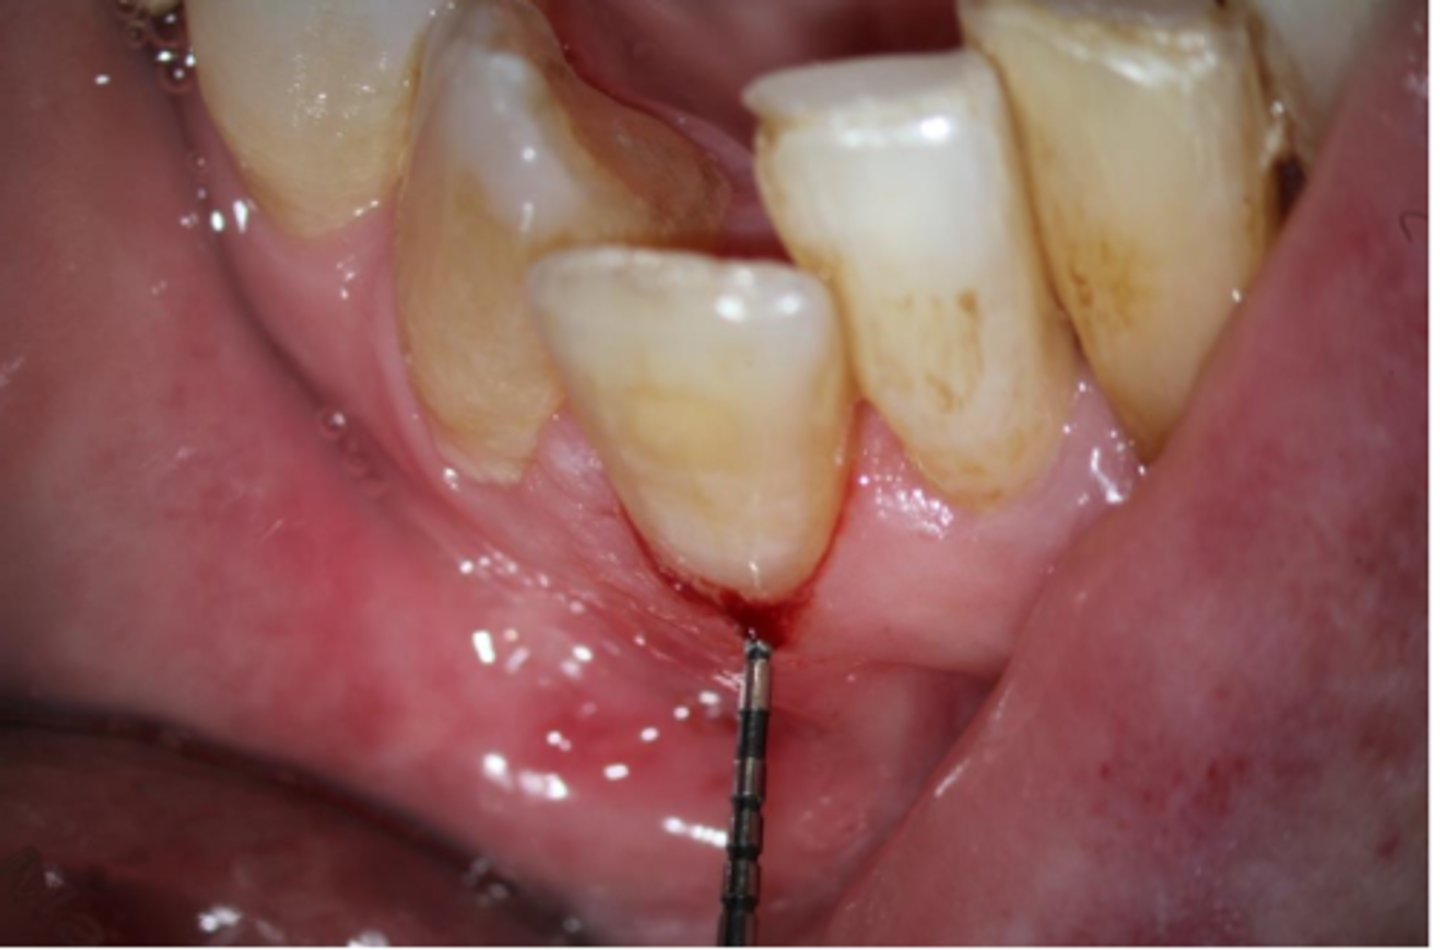

Lateral External Inflammatory Resorption

ID the type of resorption:

CLINICAL:

- History of trauma

- Pulpal Dx → necrotic

- Symptoms of apical periodontitis

- - May be tender to percussion and/or palpation

RADIOGRAPHIC:

- Radiolucent, crater shaped indentations on the root surface with adjacent bone loss and periradicular radiolucencies

Patient presents with history of trauma, does not respond to sensibility tests (necrotic pulp), is tender to percussion and/or palpation and has these radiographic findings. What is the most likely diagnosis?